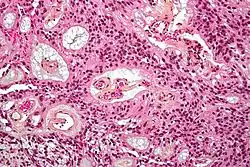

Micrograph of an ependymoma. H&E stain.

Ependymomas are composed of cells with regular, round to oval nuclei. There is a variably dense fibrillary background. Tumor cells may form gland-like round or elongated structures that resemble the embryologic ependymal canal, with long, delicate processes extending into the lumen; more frequently present are perivascular pseudorosettes in which tumor cells are arranged around vessels with an intervening zone consisting of thin ependymal processes directed toward the wall of the vessel.[5]

It has been suggested that ependymomas are derived from radial glia, despite their name suggesting an ependymal origin.[6]